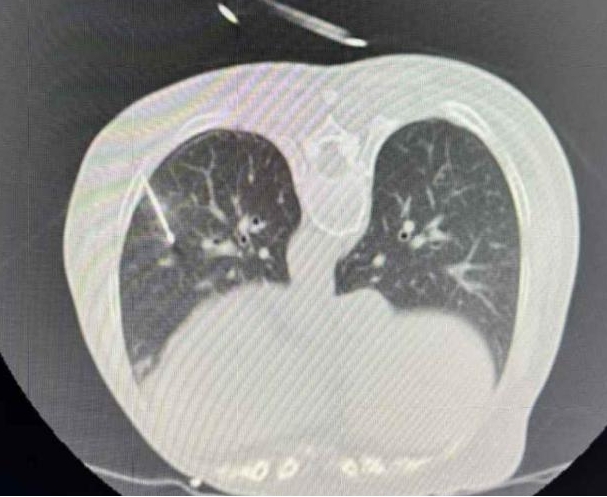

患者张某,64岁,体检发现左肺两处1.2cm结节,经多学科会诊评估后,胸外科团队决定采用射频消融术。手术在局麻下进行,通过CT精准定位,将射频电极针穿刺至结节部位进行消融。手术历时1小时,成功消除病变组织,患者术中无疼痛感,术后恢复良好。